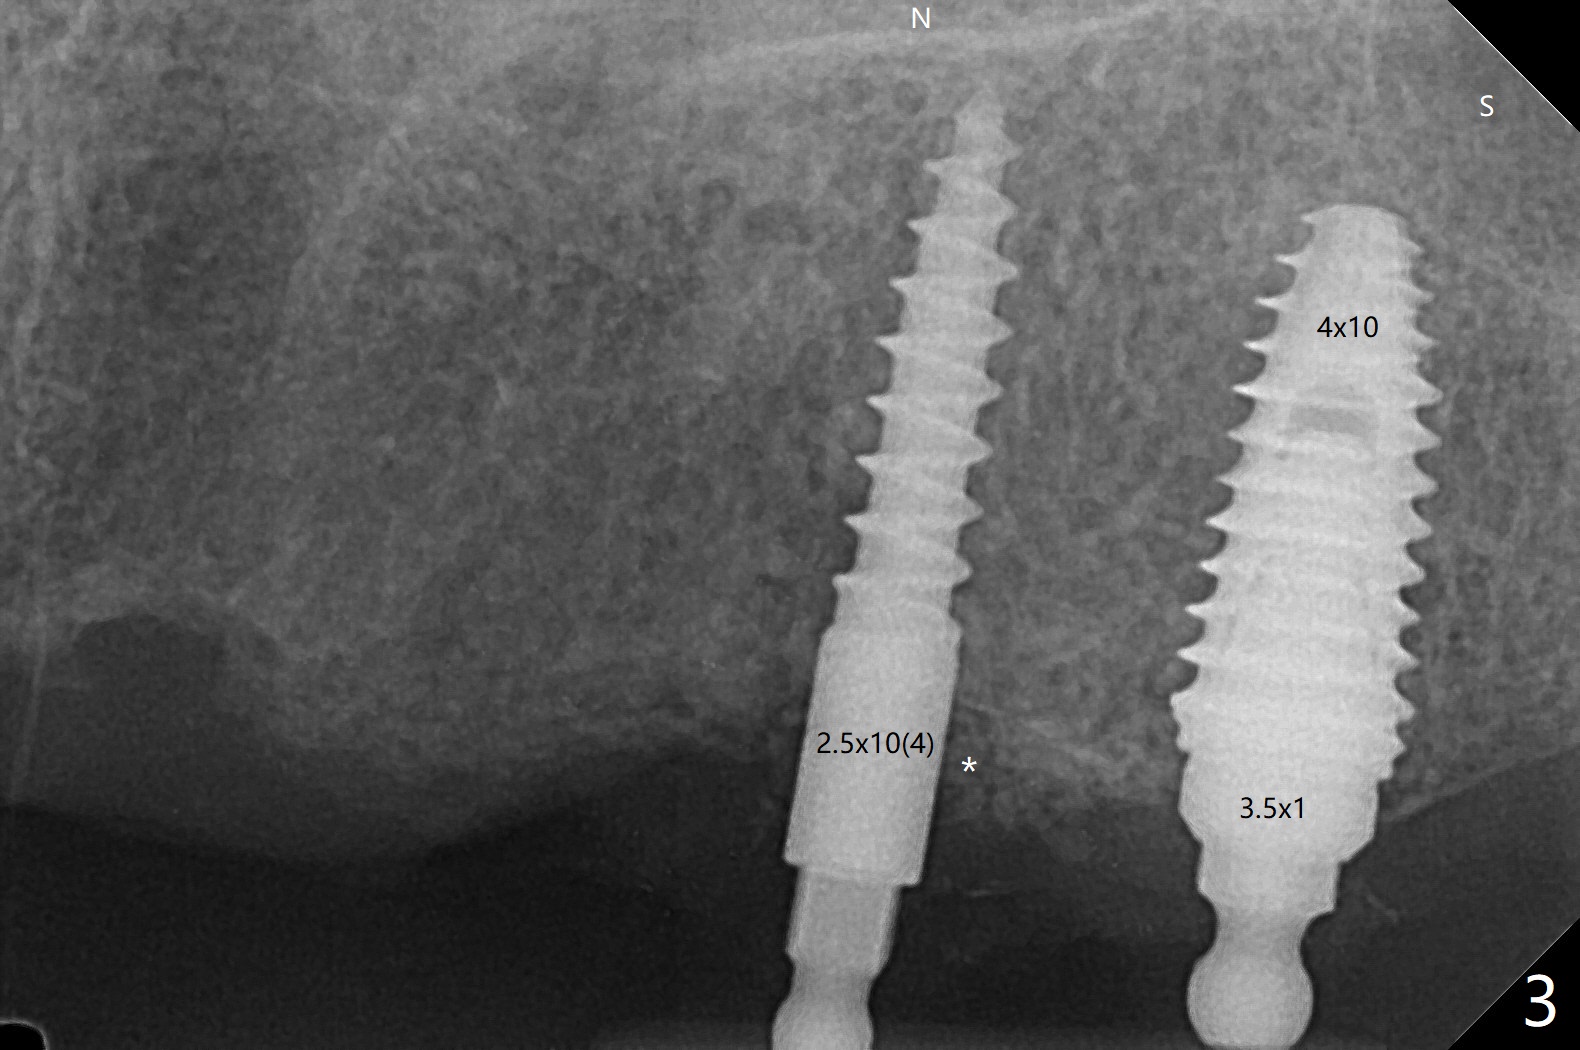

63岁女有上下活动局部假牙,由于右下侧切牙折裂(26号牙)就诊,保守处理(重新粘固)。虽然病人满意上颌义齿,而且非常害怕牙科治疗,并不想多花钱,但是对左上两个植牙固位假牙有兴趣。原计划在尖牙和第二双尖牙(11和13号牙),CT检查表明11号牙处牙槽骨太窄,所以改为12和13处种植(3.5乘10,4乘10毫米)。12号牙处牙槽嵴截除后,颊舌侧宽度仍不够,钻洞直径2毫米(图一),似乎不得不用一体式带球帽植体(1-piece implant with ball abutment),2.5乘10(4)毫米(图二至四;N: 鼻腔,S: 上颌窦),并且在它周围植骨(图三,四 *)。在假牙相对位置创造空间后,做软衬里(图五)。对于恐惧病人,尽管带球帽植体精确度要求不高,导板还是必要的。一周以后病人十分感激,因为没有痛(图六)。术后一个月她很高兴告诉我们自从植牙后,托牙下面不容易积累食物了。